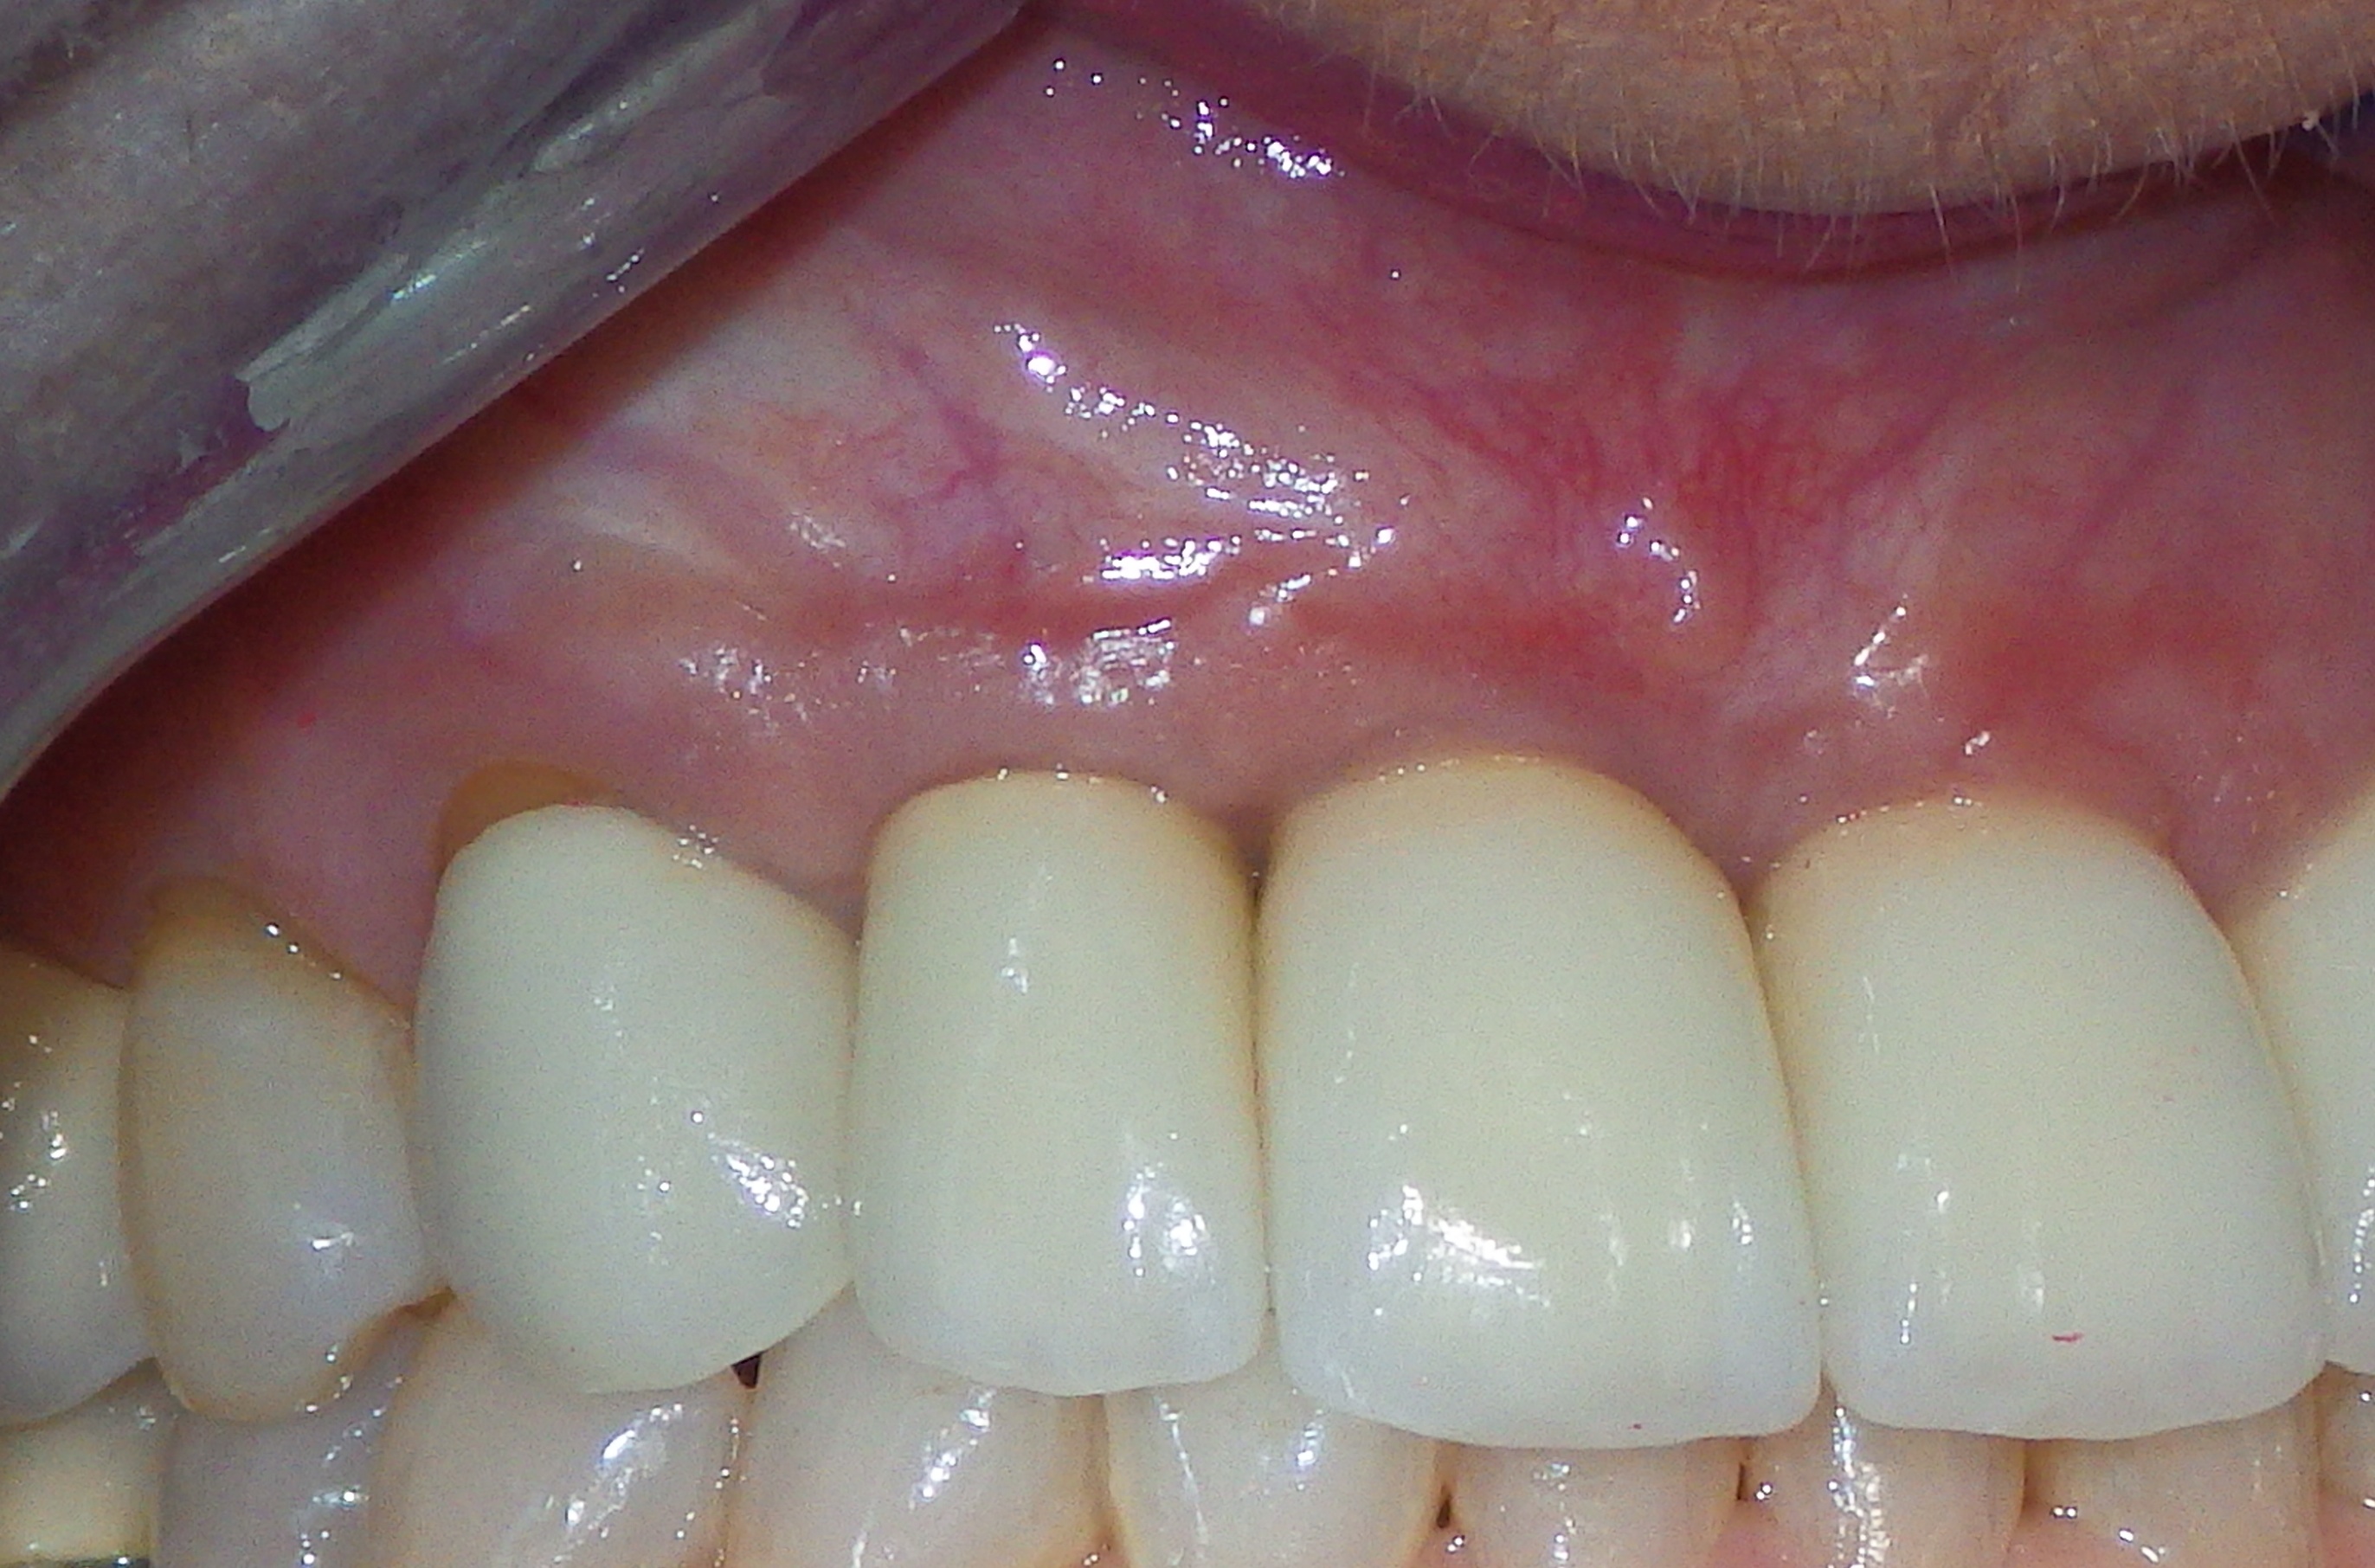

Finally, whether managing adult periodontitis or peri-implantitis (Figure 7), surgical design and soft tissue manipulation should be considered of vital importance, particularly in the maxillary anterior esthetic zone. Careful attention to papilla preservation techniques23 and incision design to minimize or eliminate the potential for gingival recession are vital to maintaining a natural-looking gingival framework around the implant restoration. This includes the need for adequate keratinized tissue because, even in the most precise cone-beam computed tomography-guided implant placement procedures, studies have shown that the absence of a residual band of keratinized tissue >6 mm wide may be associated with an increase in clinical attachment loss (Figure 8) and an increase in dehiscences after 1 year.24

Fig 8. Note the lack of keratinized gingiva in a heavy smoker.

Figure 8